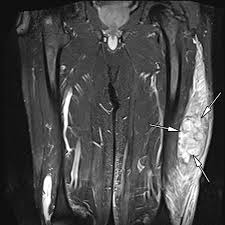

Post Mortem Imaging In Forensic Investigations Current Utility Limit Rrfms

Post Mortem Imaging In Forensic Investigations Current Utility Limit Rrfms from www.dovepress.com

Imaging Of Soft Tissue Sarcomas Patel Chinese Clinical Oncology

Imaging Of Soft Tissue Sarcomas Patel Chinese Clinical Oncology from cdn.amegroups.cn